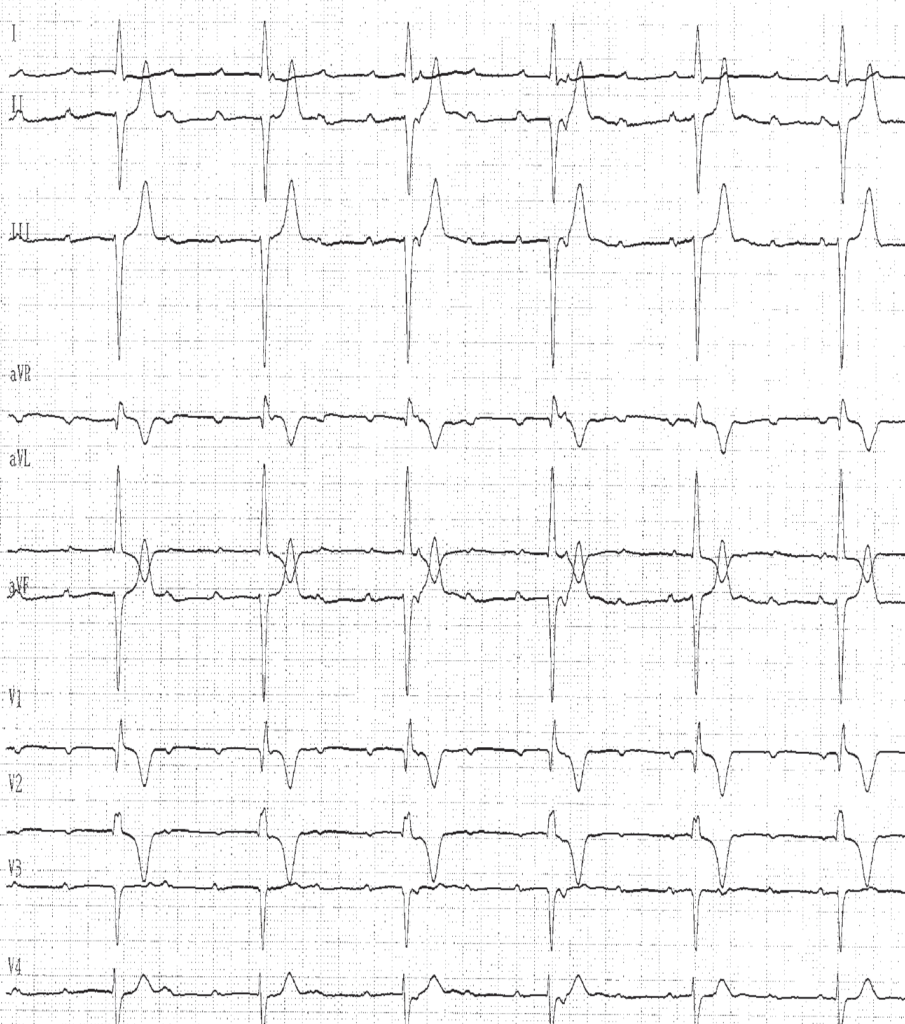

Le diagnostic de BAV complet se définit par l’interruption complète de la conduction auriculo-ventriculaire et repose sur l’existence d’une dissociation auriculo- ventriculaire, les oreillettes et les ventricules étant sous le contrôle de pacemakers indépendants, avec une fréquence ventriculaire plus lente que la fréquence auriculaire. Il n’existe pas de relation entre les ondes P et les complexes QRS, les intervalles PR sont variables sans séquence répétitive.

La fréquence de l’échappement ventriculaire est généralement régulière, non ou peu influencée par les efforts ou les manœuvres vagales. La fréquence et la durée du QRS varient en fonction du site d’échappement:

• échappement jonctionnel: l’origine de l’échappement étant haut située au dessus de la bifurcation du faisceau de His, la durée des complexes QRS est normale (inférieure à 100 ms) sauf si il existe un bloc de branche préexistant (comme chez ce patient); la fréquence ventriculaire est généralement modérément ralentie (entre 40 et 50 battements par minute);

• échappement du faisceau de His ou d’une des branches: l’origine de l’échappement étant située soit au niveau du faisceau de His, soit au-dessous de la bifurcation sur une des branches, le QRS peut être fin (échappement du His) ou large avec un aspect de boc de branche (His + bloc de branche ou échappement d’une branche); la fréquence ventriculaire est généralement ralentie (entre 30 et 40 battements par minute);

• échappement ventriculaire: l’origine de l’échappement étant bas située et correspondant à un foyer idioventriculaire, la durée des complexes QRS est très élargie (entre 140 et 200 ms) et ne rappelle que très grossièrement l’aspect d’un bloc de branche et est qualifiée de retard droit ou de retard gauche; la fréquence ventriculaire est très ralentie (parfois inférieure à 20 battements par minute).

Le rythme auriculaire est le plus souvent sinusal même si on peut observer une fibrillation auriculaire ou un flutter atrial. Le rythme sinusal est parfois accéléré, la fréquence auriculaire ayant tendance à être d’autant plus rapide que la fréquence ventriculaire est lente par une réaction réflexe du nœud sinusal à la bradycardie ventriculaire.